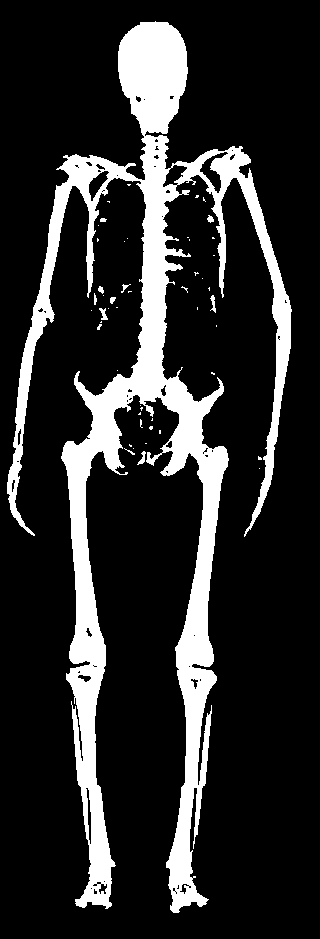

The key problem, however, is obtaining training data that simultaneously gives the inside and outside of the body in 3D. Most imaging technologies that simultaneously capture the inside and outside of the body use ionizing radiation, which is harmful to humans; e.g. Computed Tomography (CT) and X-rays. This means that such data is extremely limited, preventing learning-based methods. Our insight is to use dual-energy X-ray absorptiometry (DXA) data. DXA scans use low-dose X-rays to measure bone mineral density and body fat composition. The radiation level is so low that it is certified to be used on healthy patients for clinical studies, such as the UK Biobank [36]. In a DXA scan, two images are computed by combining two different energy levels: a soft-tissue image and a bone image (Fig. 2). In the silhouette of the body can clearly be seen, whereas reveals the structure and shape of the bones.

From the input images (, ), we compute the corresponding skin and skeleton segmentation masks (, ). For the skin mask , we threshold . As some small artifacts remain, mainly due to pixels in the lungs with low intensity values, we detect the closed contours on the image and fill in small areas. In Fig. 2 we show pairs of input and the obtained mask .